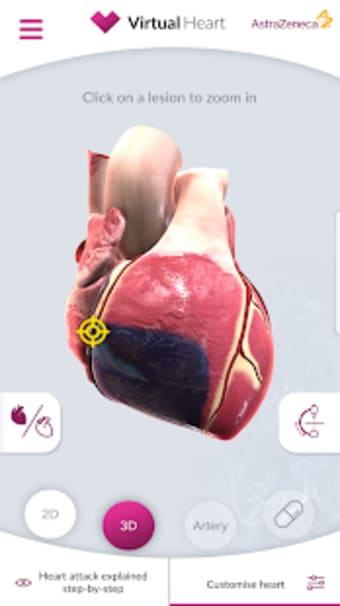

Virtual Heart - ANZ är en gratis programvara för Android, som ingår i kategorin 'Medical'.Om Virtual Heart - ANZ för Android

Virtual Heart - ANZ är tillgänglig för Android 9.0 eller högre. Den nuvarande versionen av programmet är 2.2, och du kan köra den endast på engelska.